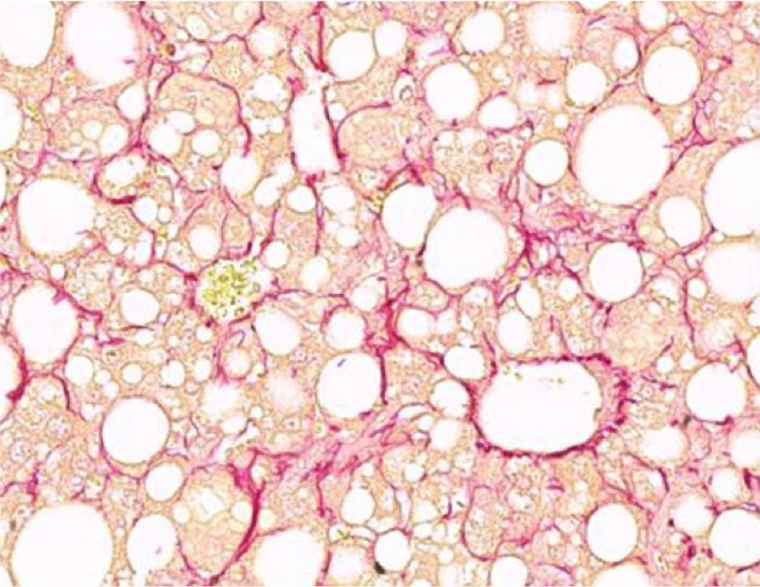

Die nichtalkoholische Fettlebererkrankung ist die häufigste Lebererkrankung weltweit und tritt bei etwa 25 Prozent der Weltbevölkerung auf. Mehr als 90 Prozent der Übergewichtigen, 60 Prozent der Personen mit Diabetes und bis zu 20 Prozent der Normalgewichtigen entwickeln die Krankheit. Ihr Hauptmerkmal ist die Ansammlung von Fett in der Leber. Eine Leber kann verfetten und dennoch normal funktionieren. Allerdings können die Fettansammlungen auch zu einer nichtalkoholischen Steatohepatitis führen – einer aggressiven Form der nichtalkoholischen Fettlebererkrankung, die mit Entzündungen und mitunter Fibrose einhergeht. Die nichtalkoholische Steatohepatitis wiederum kann zu weiteren Komplikationen wie Leberzirrhose und primärem Leberkrebs führen und lebensbedrohlich sein.

Mithilfe von Genomanalysen untersuchten die Forschenden Mechanismen, die die Entwicklung und Funktion der Hepatozyten steuern, dem am häufigsten vorkommenden Zelltyp in der Leber. „Unsere Ergebnisse zeigen, dass Hepatozyten während der Weiterentwicklung zur nichtalkoholischen Steatohepatitis einen teilweisen Identitätsverlust erleiden, sie werden umprogrammiert“, erklärt Anne Loft, Erstautorin der Studie.